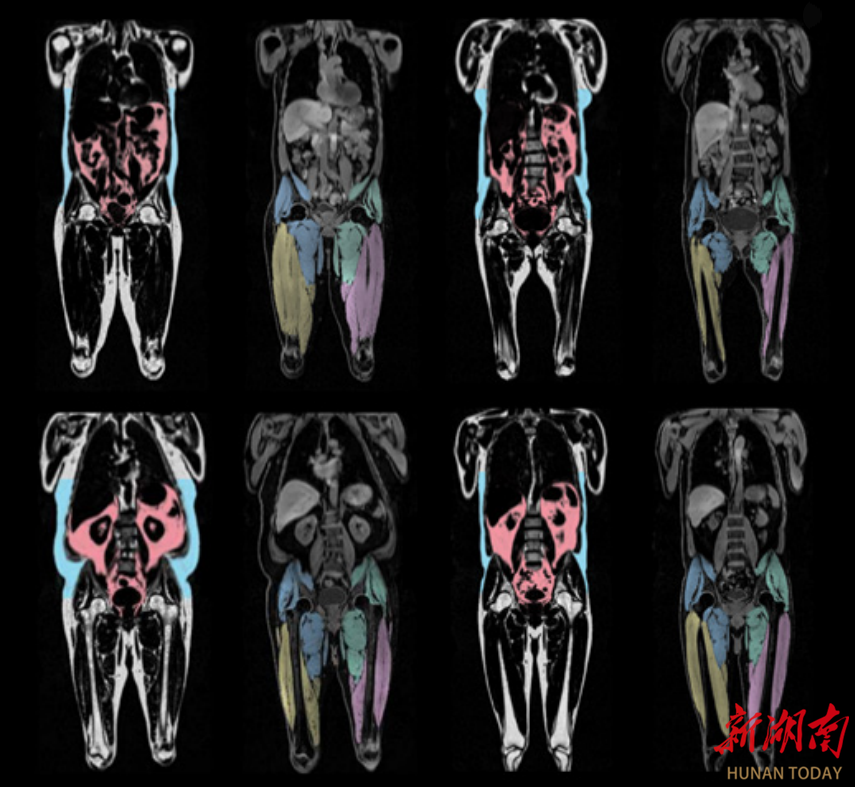

2025年8月,《欧洲心脏杂志》(EHJ)上发表的一项研究发现:内脏脂肪累积与男女心血管衰老加速相关,想要心血管衰老慢一点:一个部位要“细”——腰要细,两个地方要“粗”——臀围粗、大腿粗。

研究发现:腹部脂肪累积,会加速男性心血管衰老;腿部和臀部脂肪累积,会减缓女性心血管衰老。

具体而言,内脏脂肪每增加1升,加速心血管衰老约0.66年,女性腿部和臀部脂肪每增加1公斤,减缓心血管衰老约0.5年。

2020年,《英国医学杂志》(BMJ)上发表的一项研究分析了253万余人后发现:腹部肥胖(腰粗)的人全因死亡风险较高,而腿部和臀部肥胖(腿粗/臀粗)的人死亡风险较低。

具体来说,腰围每增加10厘米与全因死亡风险增加11%,大腿围每增加5厘米与全因死亡风险降低18%,臀围每增加10厘米与全因死亡风险降低10%。

简单来说,腰细意味着内脏脂肪少,心血管更年轻;臀粗腿粗则可能意味着肌肉量和健康脂肪充足,有助于保护心血管。